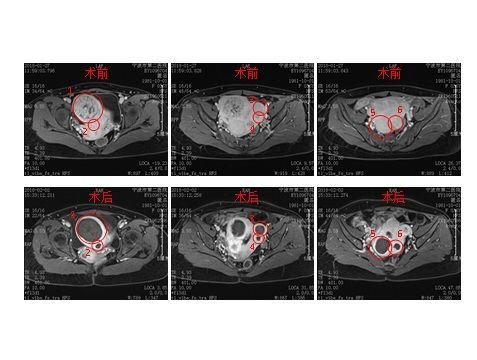

子宮肌瘤海扶治療病例

隨著我國醫(yī)學(xué)常識的不斷普及和廣大女性對生殖系統(tǒng)健康重視程度的逐漸提升,越來越多的婦科疾病在體檢中被發(fā)現(xiàn),其中,最常見的當(dāng)屬育齡女性的“子宮肌瘤”無疑。當(dāng)報(bào)告單出現(xiàn)“子宮肌瘤”的字樣后,很多女性朋友會變得很緊張。 其實(shí),子宮肌瘤是婦科常見的良性腫瘤,約有20%-25%的性成熟期婦女可檢出子宮肌瘤。寧波二院腫瘤海扶科在成立僅一年間,已完成百余例無創(chuàng)子宮海扶無創(chuàng)手術(shù),今特此擢選出一例分享大家。 女,36歲,寧波人,子宮肌瘤已發(fā)現(xiàn)近10年,因無明顯癥狀,暫未予治療,2017年12月于寧波婦兒醫(yī)院復(fù)查,行子宮B超示:“多發(fā)子宮肌瘤,最大為7cm”,患者診斷為“多發(fā)子宮肌瘤”,并出現(xiàn)輕度腹痛、尿頻、痛經(jīng)等不適癥狀,病人曾因擔(dān)心子宮肌瘤繼續(xù)增大、增多,而出現(xiàn)輕度緊張、焦慮等情緒,并且影響工作以及日常生活。 然而,如行傳統(tǒng)、或者腔鏡手術(shù)切除子宮肌瘤,不僅有復(fù)發(fā)的可能,而且有著創(chuàng)傷風(fēng)險(xiǎn);如果行子宮全切,必然會影響生活質(zhì)量,遂經(jīng)其他患者推薦來我院行海扶手術(shù)治療。